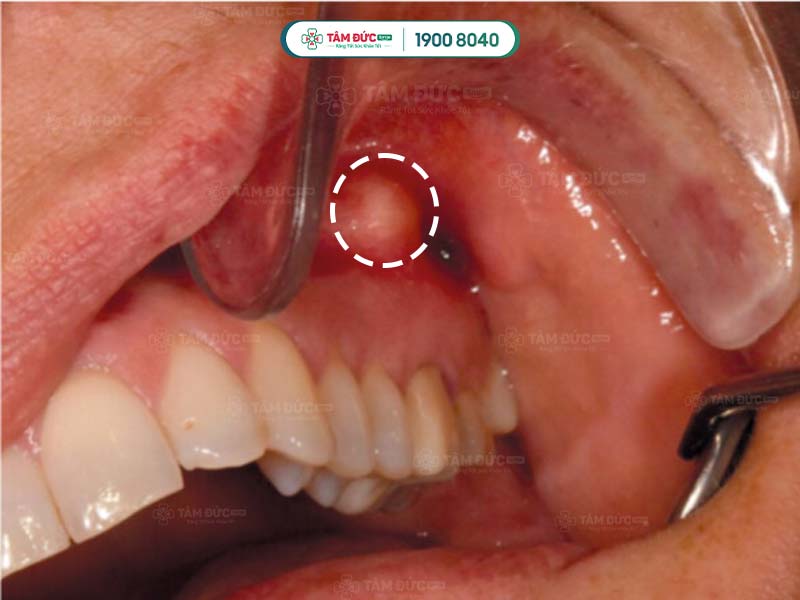

Nhiễm trùng chân răng hàm trên

Nhiễm trùng nướu răng cửa

- Áp xe răng: Đây là bệnh nhiễm trùng nghiêm trọng ở chân răng, có thể gây sưng, đỏ, đau nhức dữ dội, sốt, thậm chí là sưng mặt.